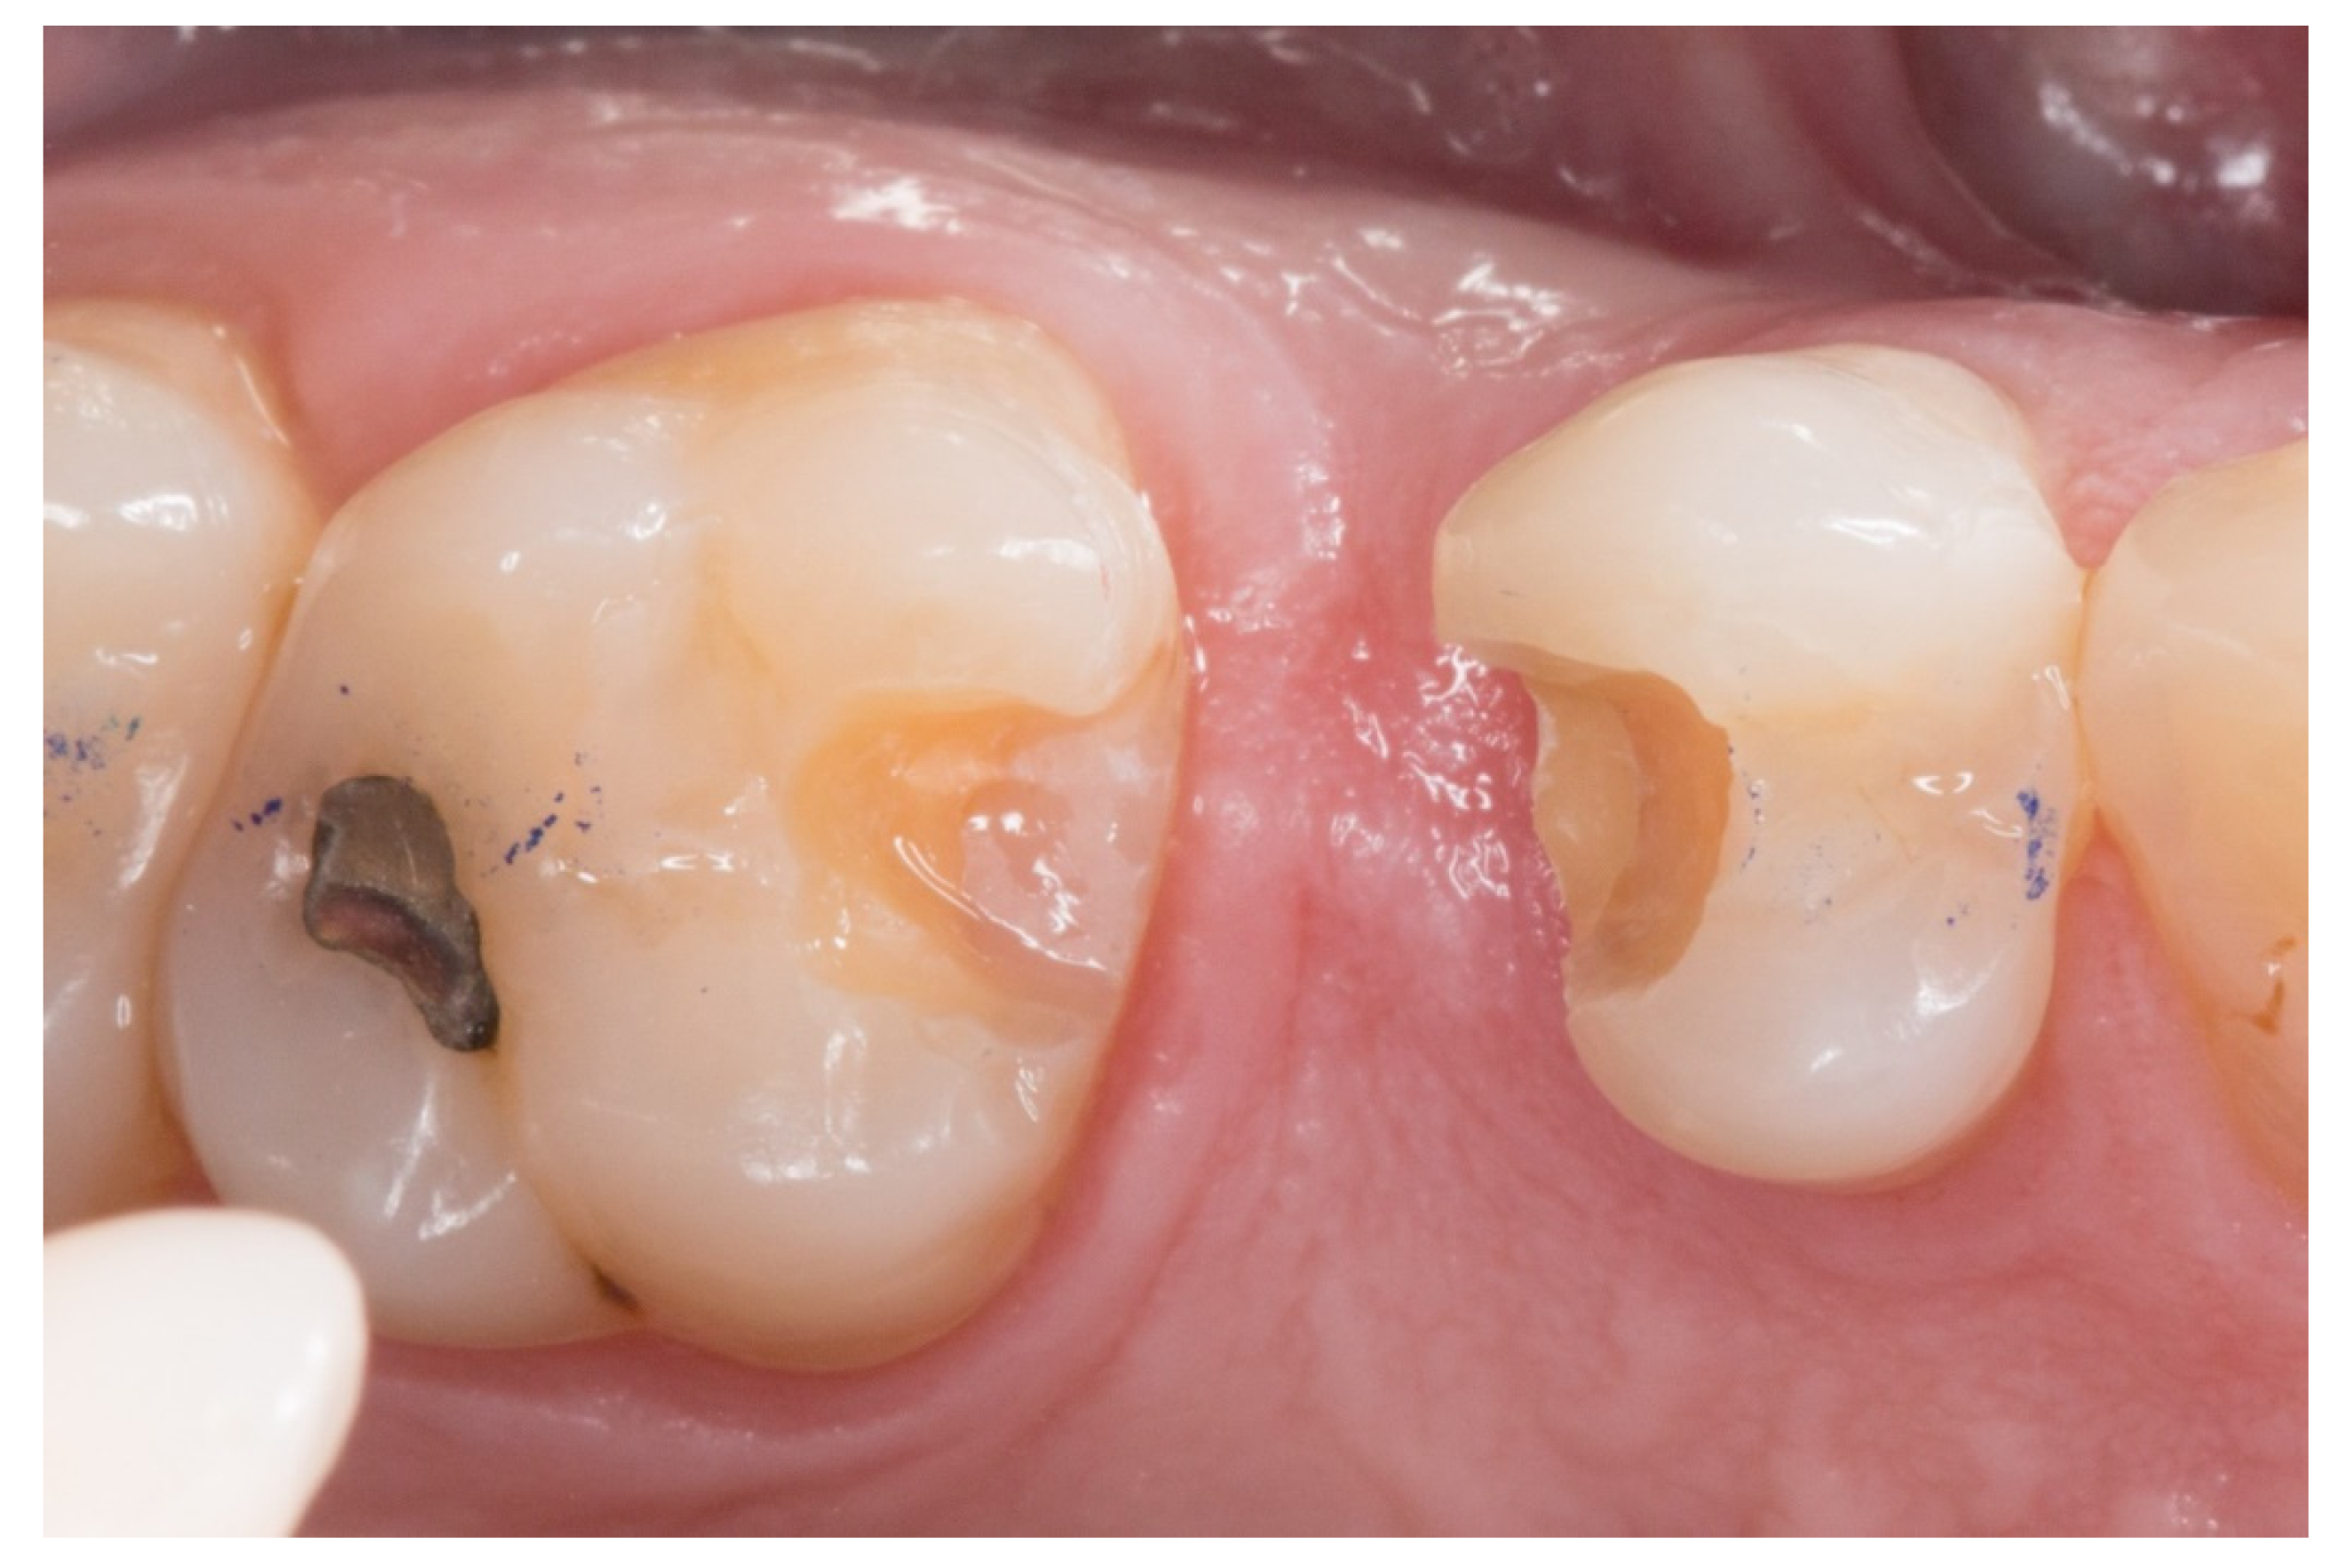

- The absence of large restorations or caries lesions on the abutment teeth;

- The periodontal inflammation aspect on the pontic area: the framework design releases the embrasures allowing adequate interproximal brushing, avoiding periodontal disease and interproximal caries.